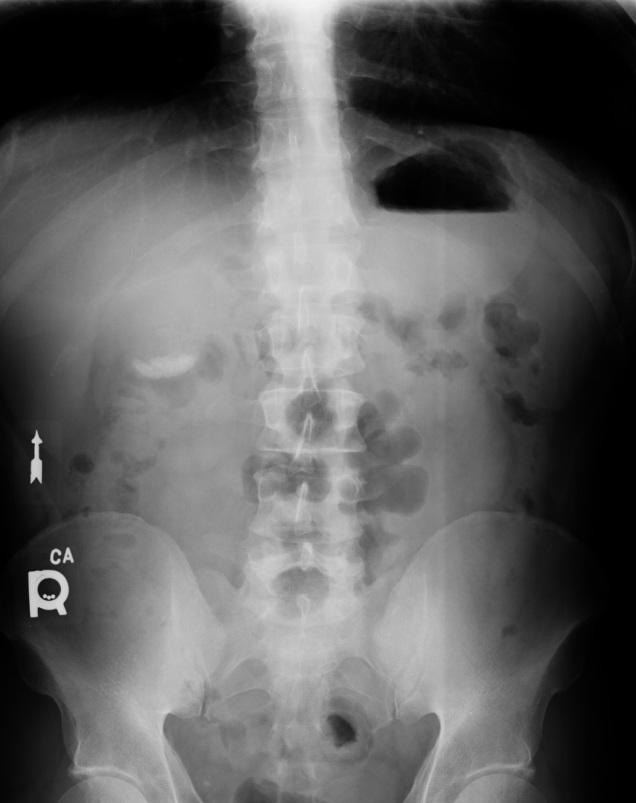

Main finding is an opaque density in the right upper quadrant. No evidence of bowel obstruction.

The appearance represents a classic milk of calcium sign. The sign represents gravity dependent layering or sedminentation of calcium deposits in suspension located within a cyst or hollow structure. Based on this location this represents milk of calcium bile. Other locations include, for example, renal cysts and breast cysts. Retained contrast from another abdominal study should be excluded before making the diagnosis.

Milk of calcium bile contains gallstones within a milky fluid containing mostly calcium carbonate. This may be secondary to long term cystic duct obstruction. Symptomatically the patient may be asymptomatic or may show signs of chronic cholecystitis. Because this usually results from chronic duct obstruction or cholecystitis, the treatment is often cholecystectomy. Untreated, the obstruction may progress and lead to the development of pancreatitis, acute episodes of cholecystitis or biliary colic, or possibly obstructive jaundice.